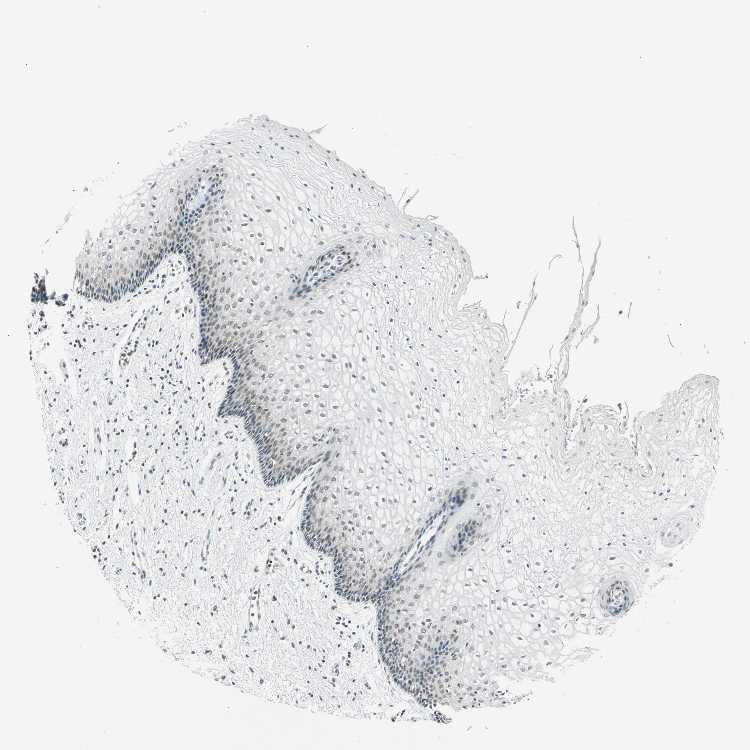

TISSUE PRIMARY DATA VAGINA Show tissue menu

VAGINA - Antibody stainingi

Antibody staining in the annotated cell types in the current human tissue is reported as not detected, low, medium, or high, based on conventional immunohistochemistry profiling in selected tissues. This score is based on the combination of the staining intensity and fraction of stained cells.

Each image is clickable and will lead to virtual microscopy that enables deeper exploration of all samples and also displays staining intensity scores, fraction scores and subcellular localization as well as patient and tissue information for each sample.

Antibody HPA067203Antibody CAB008094Antibody CAB069409

Squamous epithelial cells Not detectedNot detectedMedium